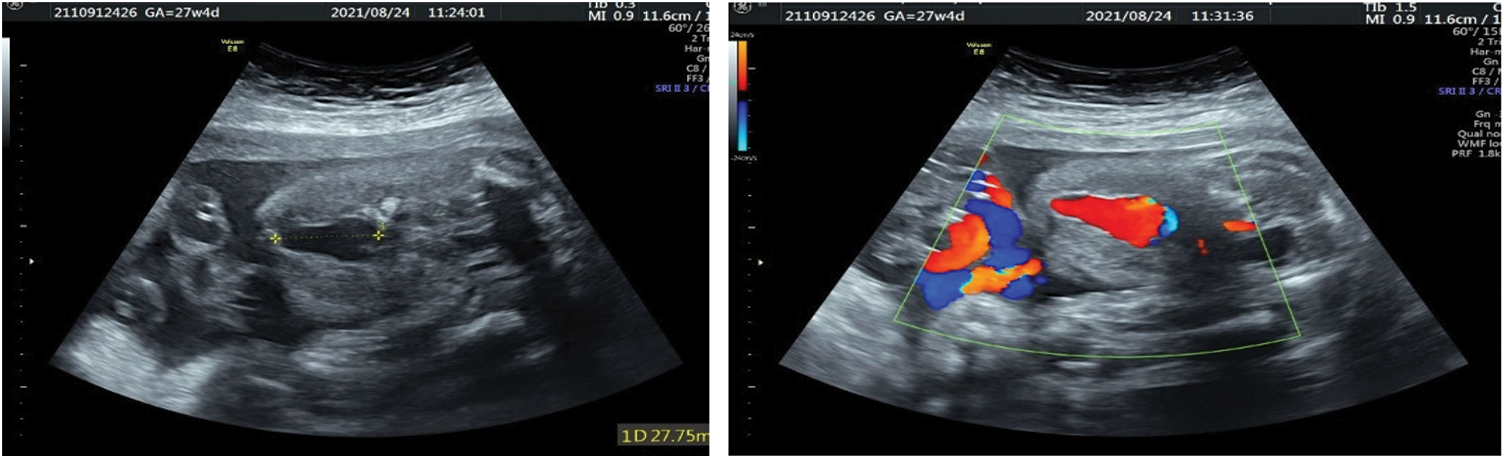

The umbilical vein varix (UVV) is relatively rare, with an overall incidence of 0.4%–1.1% [33–36]. Dilatation of the umbilical vein in the abdominal cavity of the fetus, known as intra-abdominal umbilical vein varix (Fig. 3), is common. A small number of UVV occur in the outer abdominal cavity, also known as intra-amniotic umbilical vein varix. UVV is generally limited to one segment and has a different length. Compared with the intra-amniotic UVV, the intra-abdominal UVV have a higher probability of chromosomal abnormalities [34,35]. Excluding chromosomal abnormalities and fetal structural abnormalities, the prognosis of intra-abdominal UVV is favorable, and the probability of serious complications is not high [34,35]. The extra-abdominal UVV is associated with fetal thrombosis, hematoma, obstruction of umbilical artery compression, and perinatal death [34,35]. Therefore, it is recommended that fetuses with UVV be followed weekly to 28 weeks of gestation and twice weekly thereafter to delivery at 36–37 weeks [36].

Figure 3: Fetal intra-abdominal varix at 27 weeks: Two-dimensional ultrasound showing the intra-abdominal UVV (left). Color Doppler imaging showing the blood flow pattern at the lesion (right)